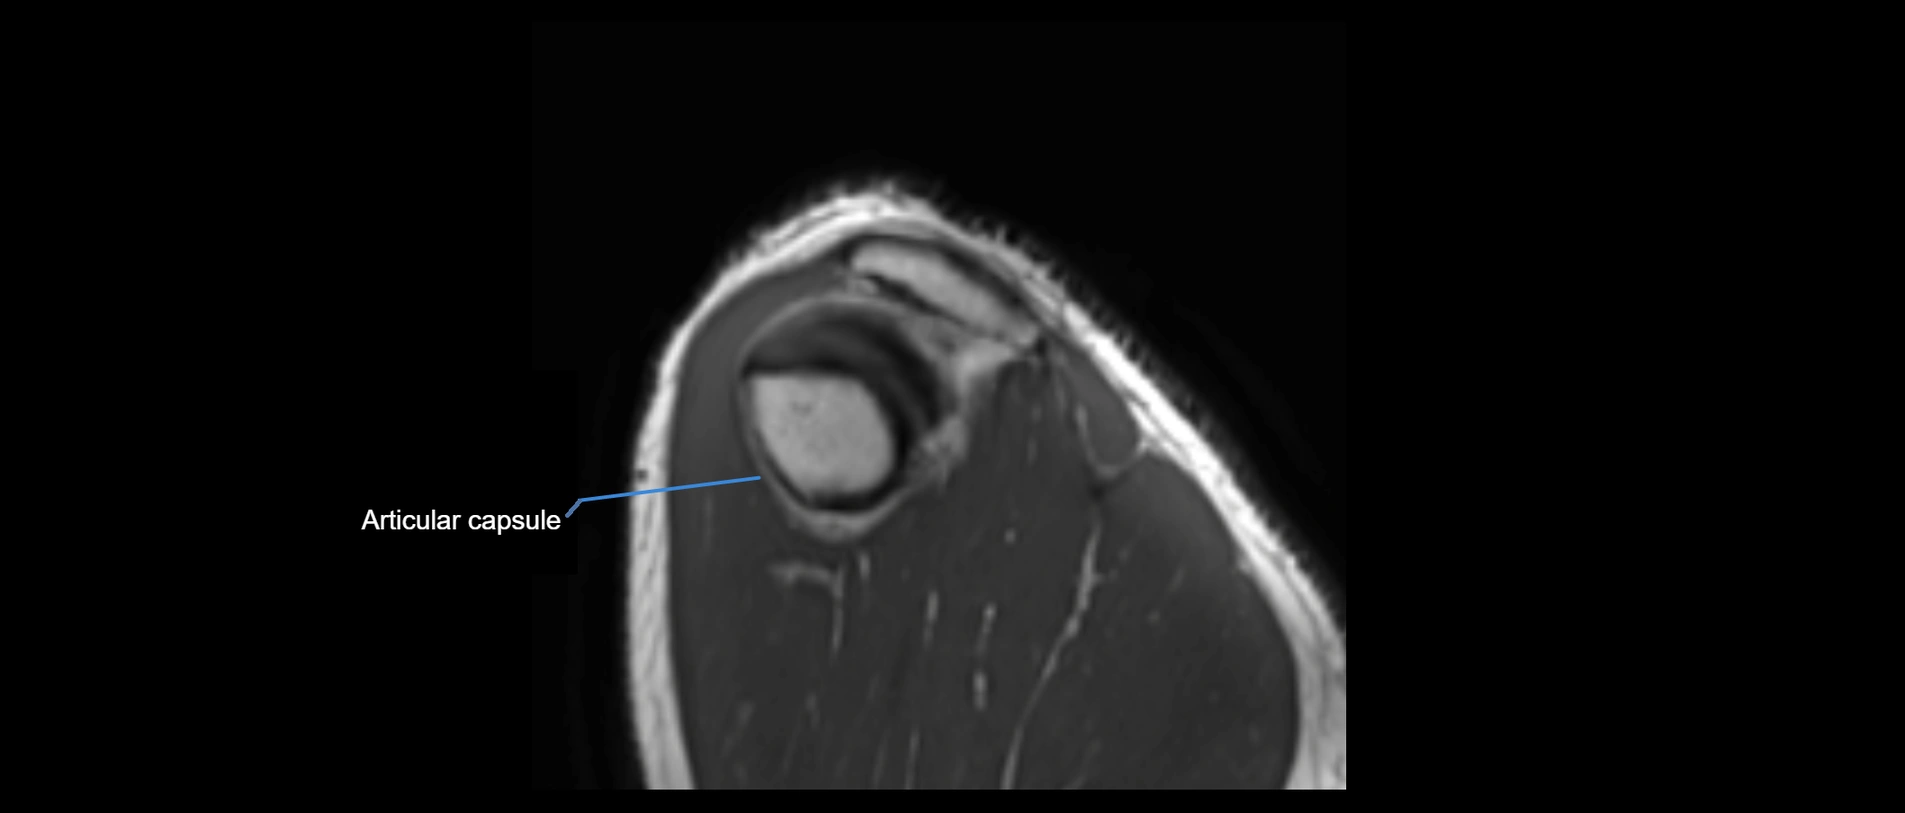

MRI images

image